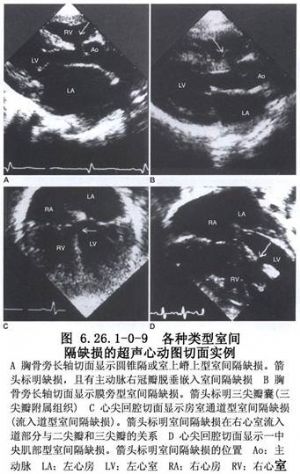

室間隔由4個部分,即膜性間隔、流入道間隔、小梁間隔、流出道間隔或漏斗部間隔組成。缺損可發生在室間隔各個部位或其交接部(圖6.26.1-0-1)。從胚胎髮育情況及分佈部位,室間隔缺損可分爲膜部間隔或膜周型間隔缺損、房室管型室間隔缺損、漏斗部或幹下型間隔缺損及肌部間隔缺損四大類型。其中膜部缺損最多見,漏斗部缺損次之,肌部缺損較少見,房室管型缺損更少見。上述各型又可分出若干亞型並有不同名稱(圖6.26.1-0-2),這種分型對手術治療有指導意義。室間隔的解剖見圖6.26.1-0-3。

(1)膜部間隔缺損:由於室間隔膜部發育或融合障礙而形成。膜部間隔從右室面觀在圓錐隔和流入道間隔之間,從左室面觀則位於左室流出道部位,又稱圓錐心室間隔,因此有人把這個部位間隔缺損又稱爲圓錐—心室室間隔缺損(conoventricular ventricular septal defect)。進一步還可分爲:

①膜部間隔缺損:僅侷限於膜部間隔的小缺損,缺損四周爲纖維結締組織,膜部間隔瘤和左室—右房通道均發生於這個部位。

②膜周型間隔缺損:位於室上嵴下方,缺損常較大,已超出膜部界限而向前、向下或向上延伸,延伸的部分均爲肌肉緣,提示這些部位的肌肉間隔未與膜部間隔融合。這類缺損在外科手術的單純室間隔缺損中約佔80%左右,並鄰近主動脈瓣右葉,其後下緣常有部分殘留的膜樣組織,房室傳導組織就從缺損後下緣的心內膜下肌肉組織中經過。

(2)房室管型室間隔缺損:又稱流入道型或隔瓣下型室間隔缺損,缺損位於三尖瓣隔瓣的下方,缺損與三尖瓣隔瓣之間無肌肉組織,並鄰近二尖瓣前瓣,房室傳導束位於缺損的下緣。也有人將這一型室間隔缺損歸入膜周型室間隔缺損,其前緣常有一部分殘留的膜樣間隔組織。

(3)漏斗部間隔缺損:缺損位於圓錐間隔上,主要由於圓錐部間隔各部融合不全所致。又分2型:

①幹下型:位於肺動脈瓣下,經缺損可見主動脈瓣,血流可直接噴流入肺動脈。

②嵴內型:位於室上嵴結構之內,四周爲完整的肌肉組織,血液直接分流入右室流出道。

(4)肌性室間隔缺損:缺損邊緣完全爲肌肉組織構成,可以發生在小梁間隔任何部位,常見於中部、尖部和前部,形態和大小不一,可以單個或多發性。嵴內型亦爲肌性缺損,另外在三尖瓣下後方亦可出現肌性室間隔缺損(圖6.26.1-0-4~6.26.1-0-7)。